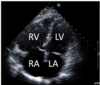

21.2 A 74-year old man in the post-anaesthesia care unit complains of chest pain. An

electrocardiogram (ECG) is performed. The occluded coronary artery is the

RCA (Inferior STEMI)

- 80% RCA

- 18% LCx

- 2% rare wrap around LAD